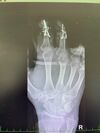

Hlavní doktor to naznačoval ale není jisté zda se chytí. Mne přišly všechny 3 ale ob den vždy 1 umřel. Mam strašně tenký cévy ci co povídal. Zde dávám foto už jsou černý všechny 3 v tydnu půjdou pryč.

Se podívej na foto co jsem sem dal :D

Tady je rtg. Fotku bez prstů sem raději dávat nebudu to už fakt velké fuj.